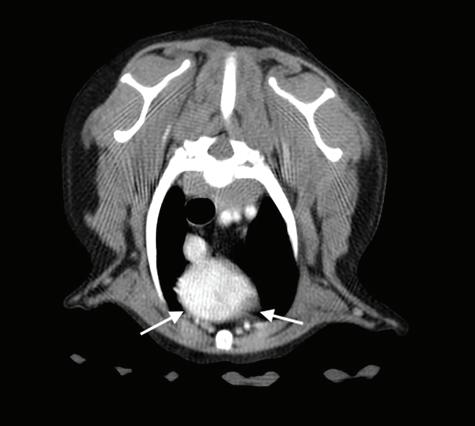

mitral (EDVM), presentando engrosamiento, prolapso e insuficiencia valvular, dilatación del atrio izquierdo (AI/AO=1,9) y leve aumento de las dimensiones diastólicas del ventrículo izquierdo normalizado al peso del paciente (NLVDD=1,7). Las presiones de llenado intracardiacas se estimaron como normales, ya que el flujo transmitral presentó un patrón de relajación anómala y la velocidad pico de E fue de 0,8 m/s. En función de estos hallazgos se confirmó el diagnóstico de enfermedad degenerativa valvular mitral con cardiomegalia izquierda y sin hallazgos compatibles con insuficiencia cardiaca congestiva, por lo tanto en estadio ACVIM B2. En las vistas ecocardiográficas paraesternal derecha de 4 cámaras y apical izquierda de 4 cámaras se visualizó una estructura redondeada y anecógena de 15 mm, con flujo sanguíneo en Doppler color, adyacente al corazón (Fig. 2). Este hallazgo es compatible con dilatación aneurismática de las estructuras vasculares o las cavidades cardiacas, si bien no

Figura 2. Ecocardiografía. (A) Vista apical izquierda de 4 cámaras optimizada para ADD. Engrosamiento de la válvula mitral (VM), dilatación moderada de atrio izquierdo (AI) y ventrículo izquierdo (VI). Estructura redondeada y anecógena de 15 mm con flujo sanguíneo (AAD), adyacente al corazón. AD: atrio derecho. (B) Vista paraesternal derecha de 4 cámaras optimizada para el atrio izquierdo. Estructura redondeada y anecógena (AAD) asociada al corazón. AD: atrio derecho.

A B

Figura 5. Imágenes de Tomografía Computarizada. Inmediatamente tras la administración de contraste (A) en ventana de tejido blando. Se observa una estructura quística en la zona craneal del atrio derecho y que contacta con la aurícula derecha, rellenándose de contraste inmediatamente tras su administración (flechas blancas). (B) Imagen reconstruida en volumen rendering, donde se visualiza el aumento de tamaño de la aurícula derecha (flecha blanca).